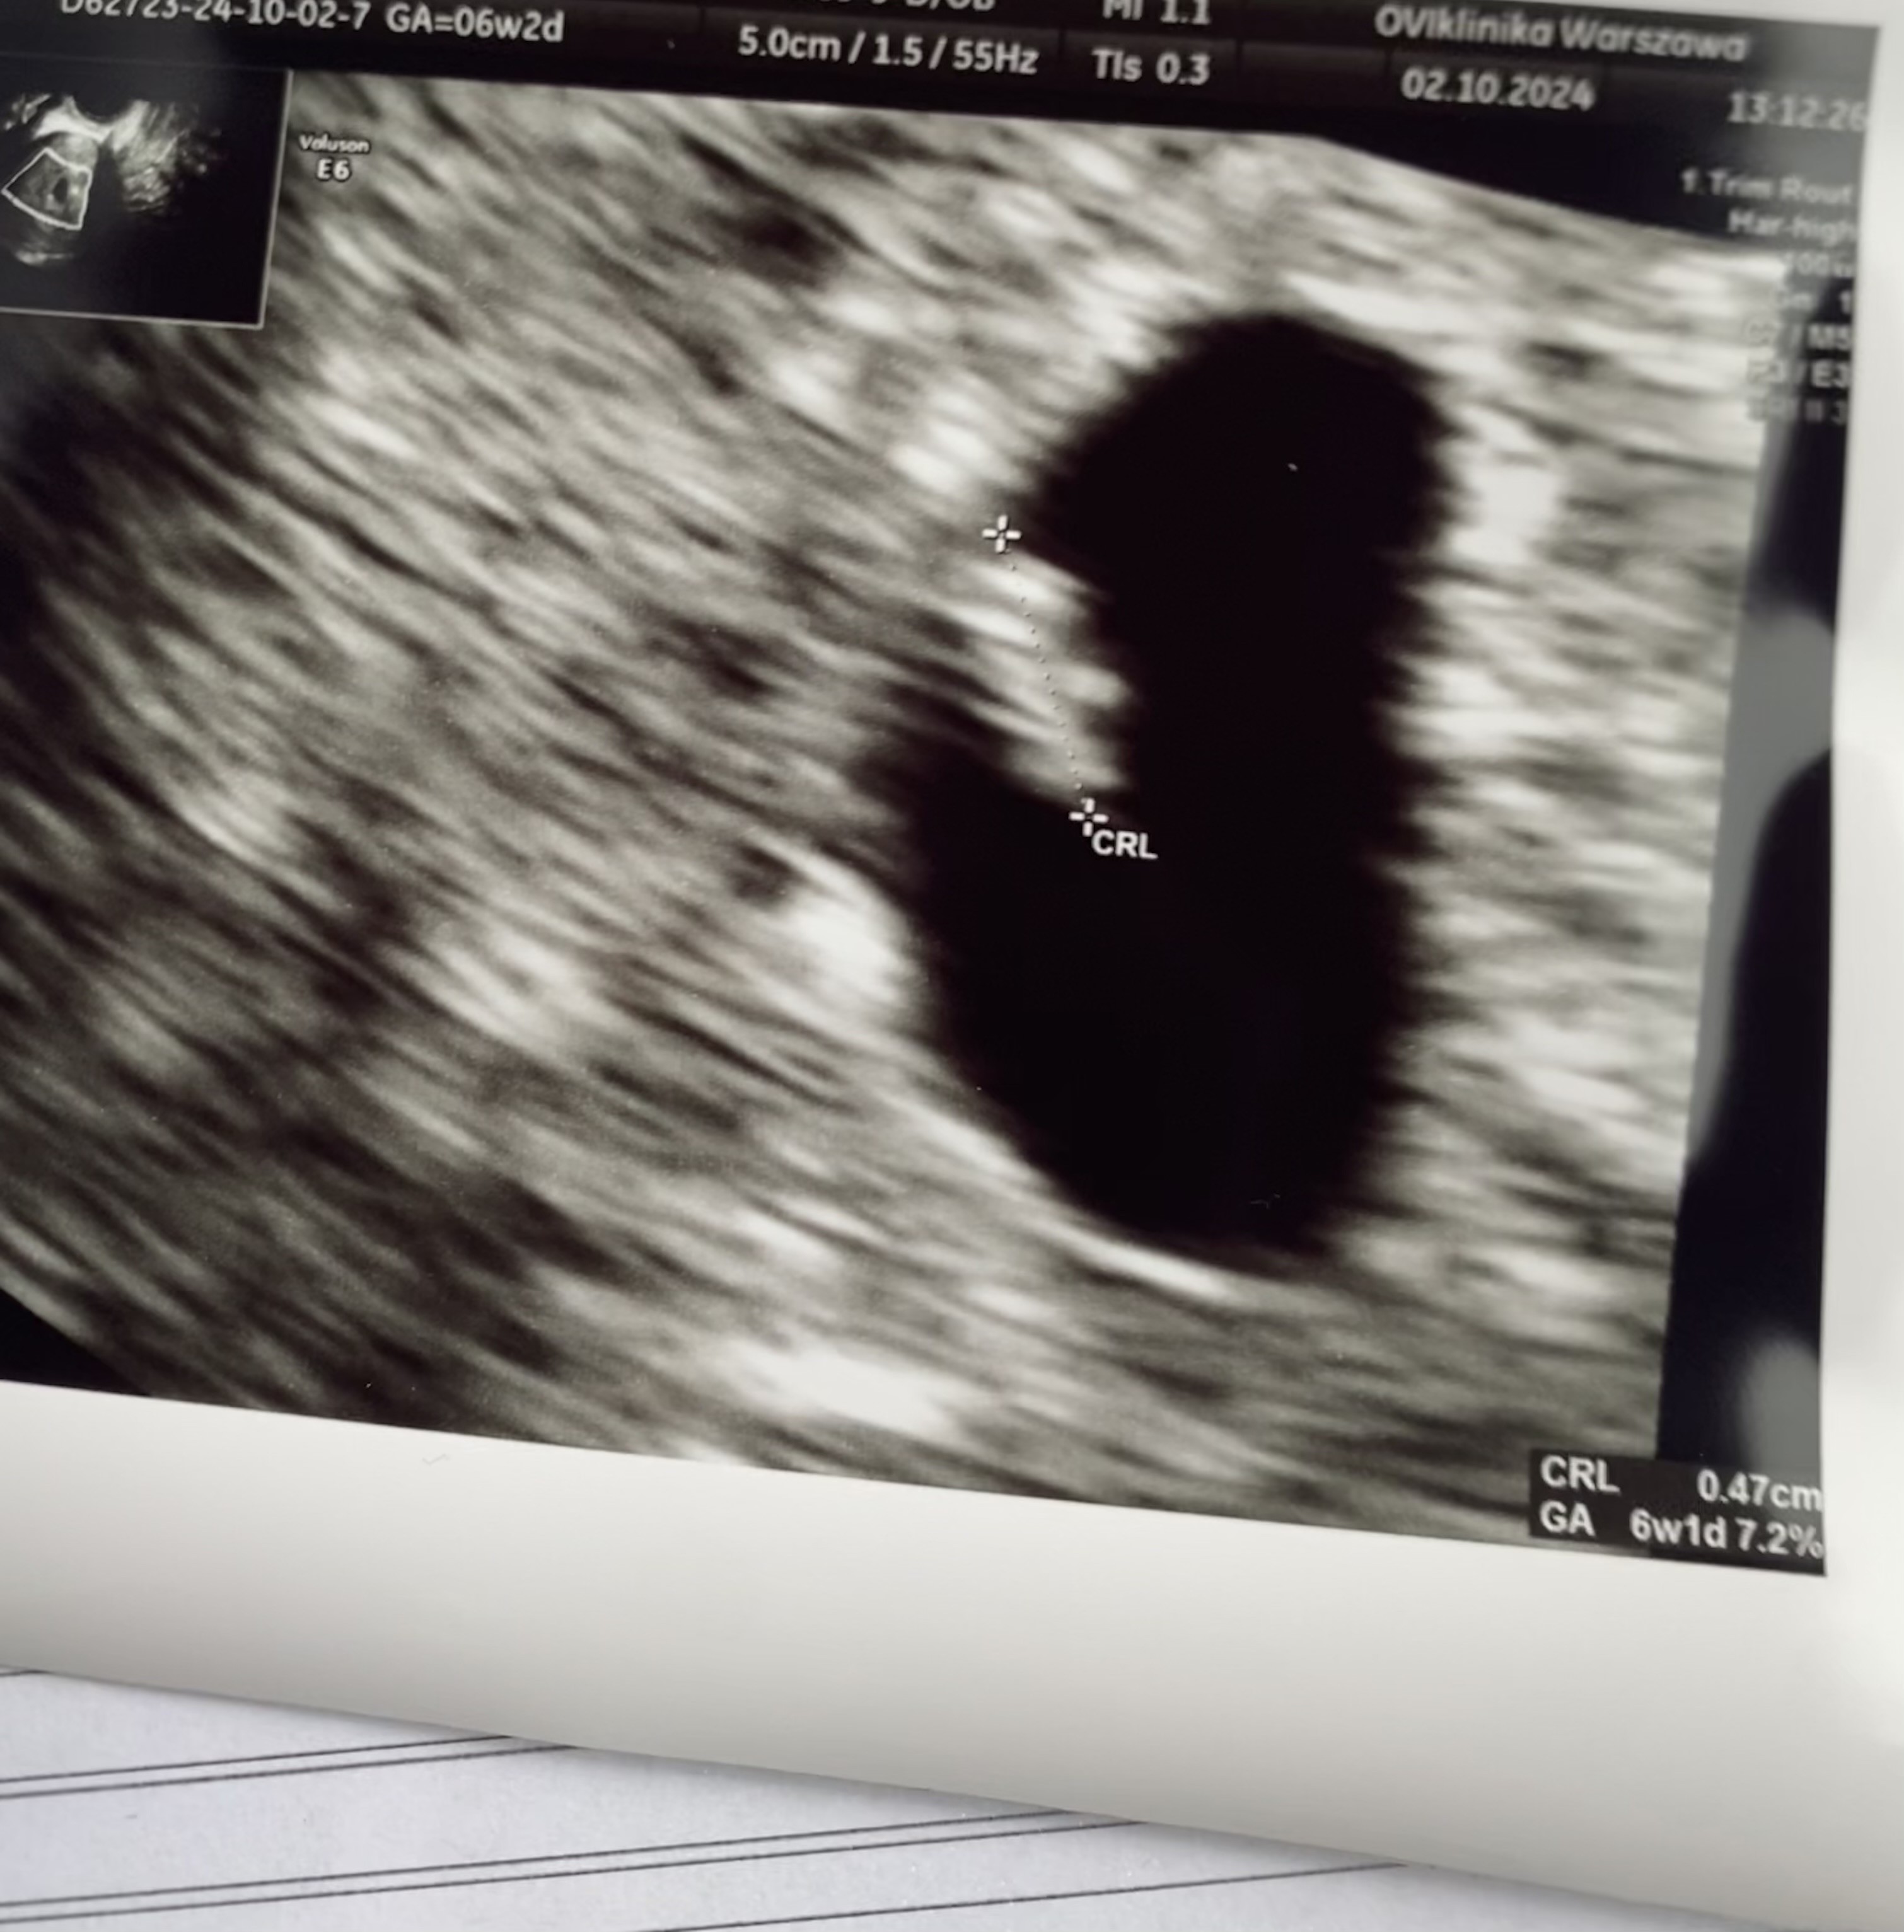

Mały wielki człowiek serduszko

Super, przypomnij mi kiedy masz termin?Mały wielki człowiek serduszkopieknie bije wszystko jak w najlepszym porządku

To jesteś trzy dni przede mną. Ja wczoraj byłam i był już zarodek z YS, ale jeszcze bez akcji serca. Jutro idę na kolejne usg i mam nadzieję, że już coś będzie, będę 6+0.27 majawizyta teraz 16 października